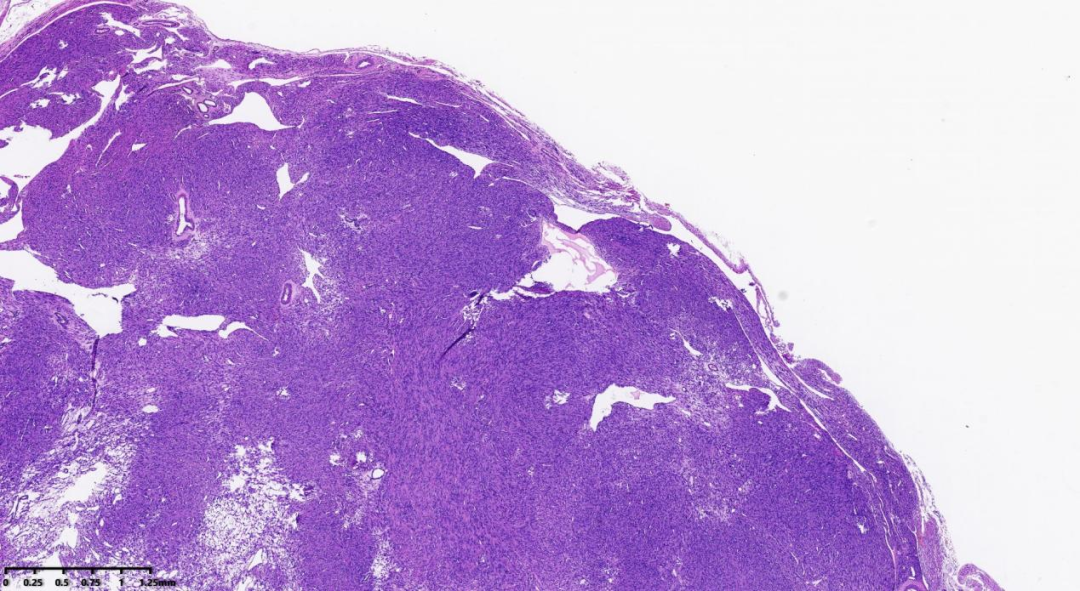

肿瘤细胞密度相对较高,肿瘤间质出现鹿角样血管

肺泡样水肿结构

肿瘤细胞密度相对较高;间质内常出现鹿角样血管;由于间质常伴有水肿,故形成肺泡样水肿结构;散在分布奇异型细胞及多核细胞;细胞核呈卵圆形;细胞核有时出现链状排列;可见胞质内嗜酸性小体;细胞核中可见突出的嗜酸性核仁,且核仁周围可见空晕。

常为轻度的核不典型性,核分裂象<5/10HPF。